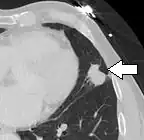

- Pleural retraction is far more common in cancers.[9] It is the pulling of visceral pleura towards the nodule.[9]

-

Nodule with pleural retraction.[9] -

In this case, pleural retraction is seen as a triangular fat component.[9]